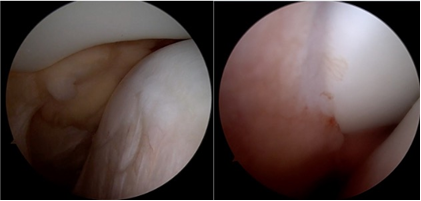

The patient was given a Long Knee immobilizer along with analgesics and was discharged home. He was advised to undergo an MRI of the right knee after 72 h once the swelling subsided. The MRI was done and along with the osteochondral defect and bony edema, the MRI showed a complete tear of the MPFL. Fig. 4,5

Figure 4: Magnetic resonance imaging of right knee – axial cuts.

Figure 5: Magnetic resonance imaging of right knee – coronal and sagittal cuts.